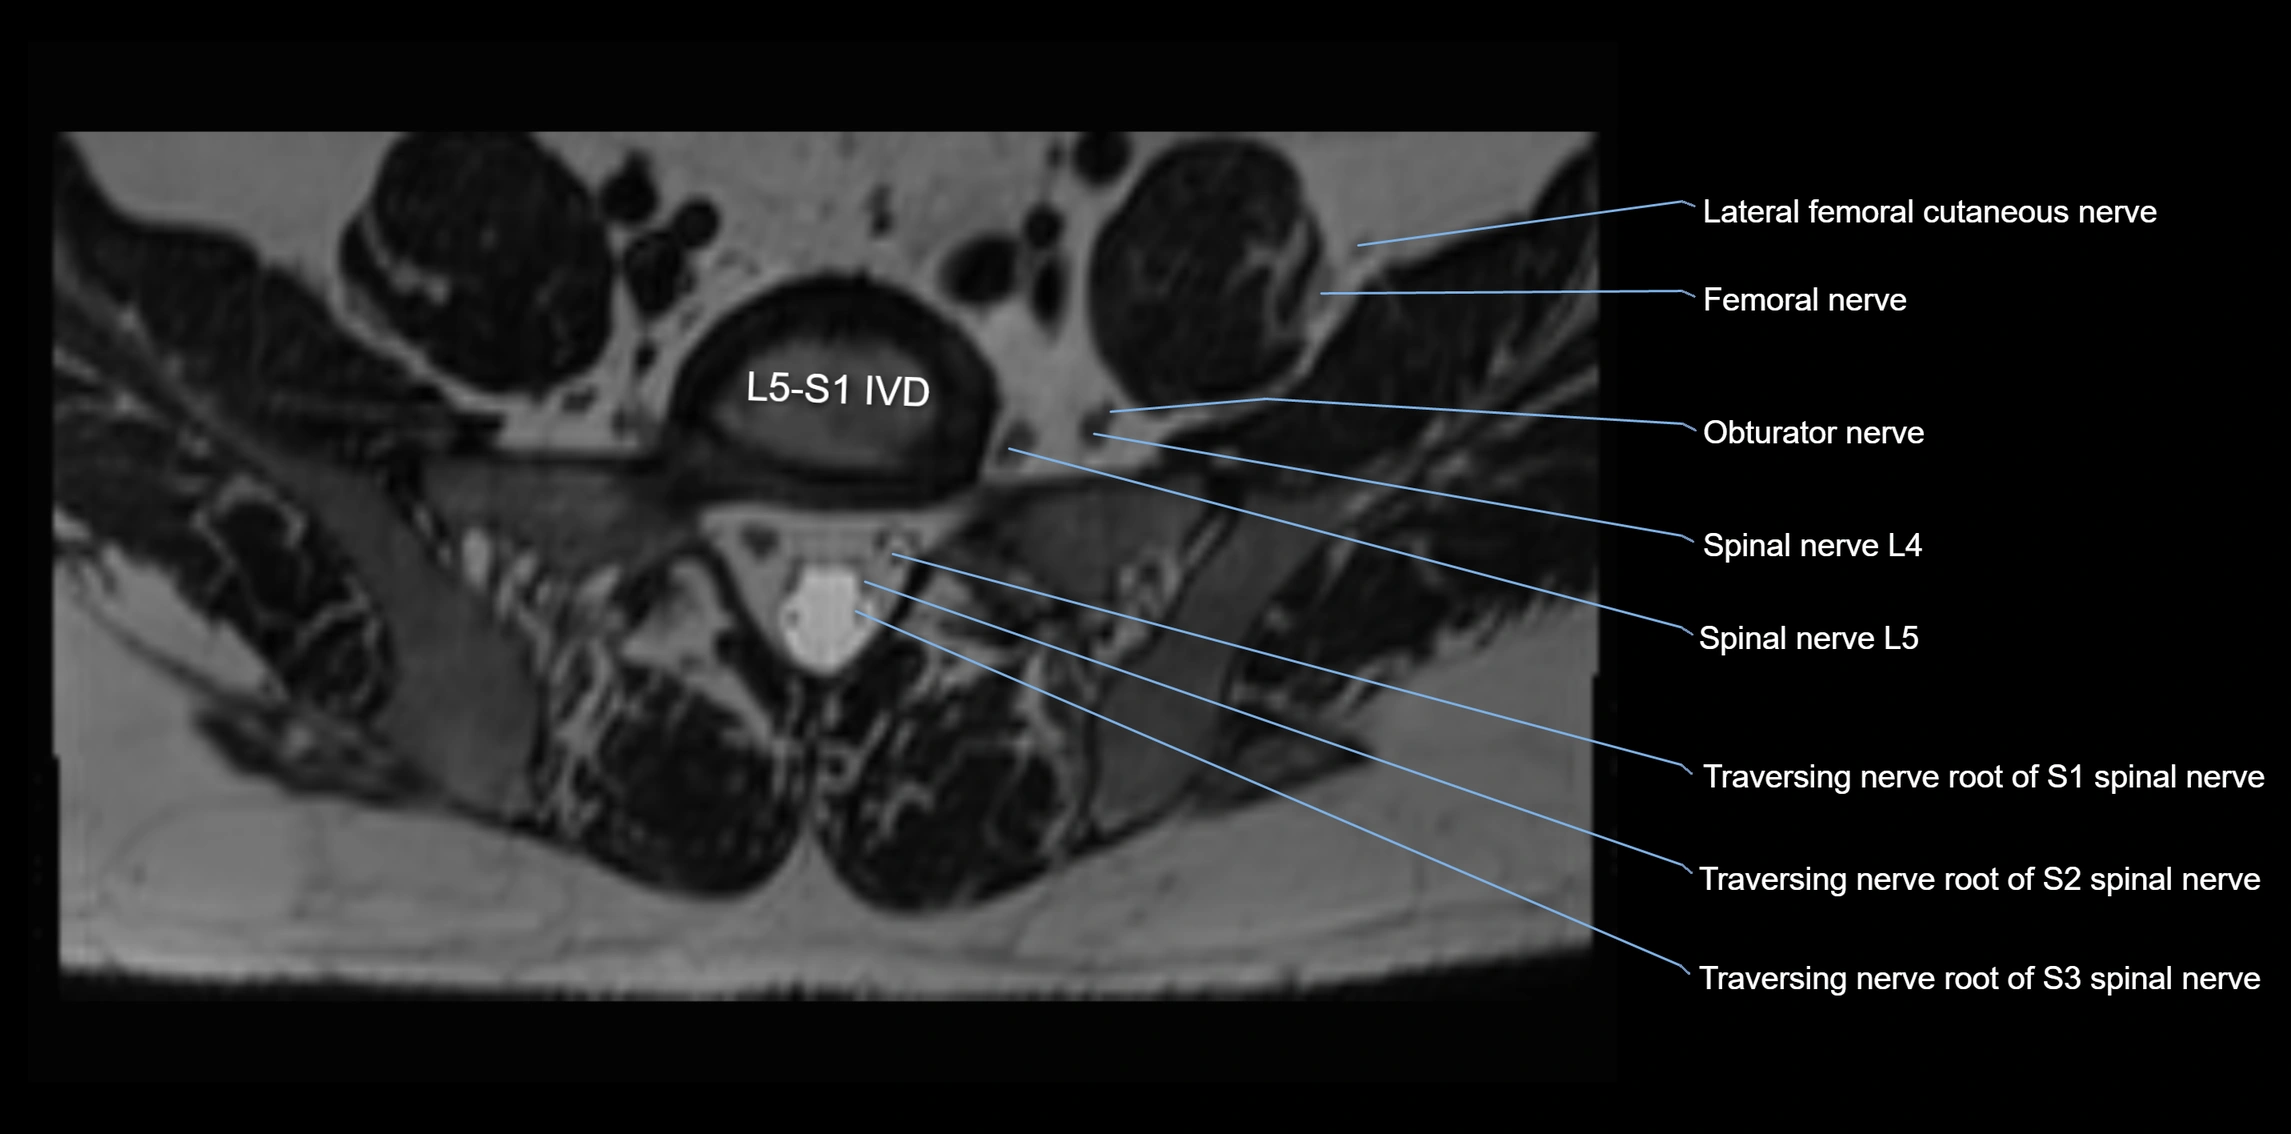

MRI image

image